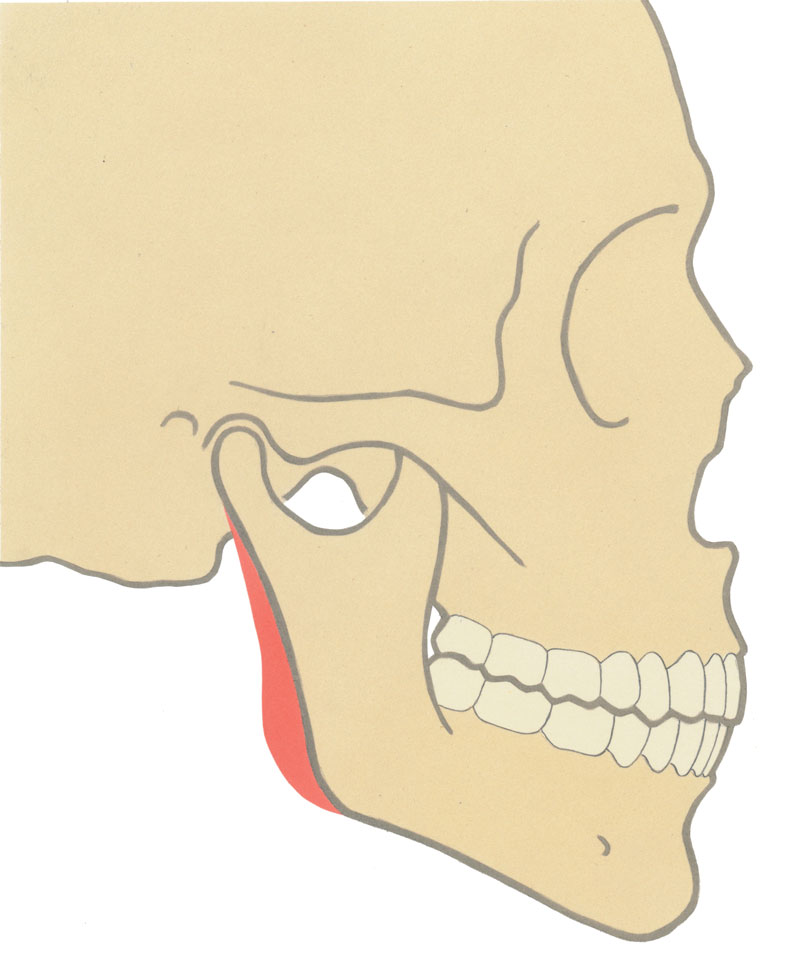

The mean angle in males is 128° (+/- 2.36°) and in females, 126° degrees (+/- 2.41°) [2]. Interestingly, the mean values are uniform for both sexes but the angle is subject to bias. A relatively short vertical or horizontal mandibular component may result in an obtuse angle (Figure 1). Contemporary literature addressing the transverse relationship is limited. In the frontal view, the mandibular angle is influenced by skeletal form, masseteric muscle volume and the overlying skin drape. There is a growing trend among female actresses, such as Olivia Wilde and Angelina Jolie, to show a relatively wide intergonial distance. These subtle facial traits are steadily filtering down to the desires of patients and the shape of the mandible is becoming an increasingly important gender determinant and makes the sole reference of the gonial angle obsolete.

Figure 1: a) Normal projection.

Figure 1:b) Reduced ascending ramus height.

Figure 1: c) Reduced horizontal body length.

Figure 1: d) Lateral deficiency.